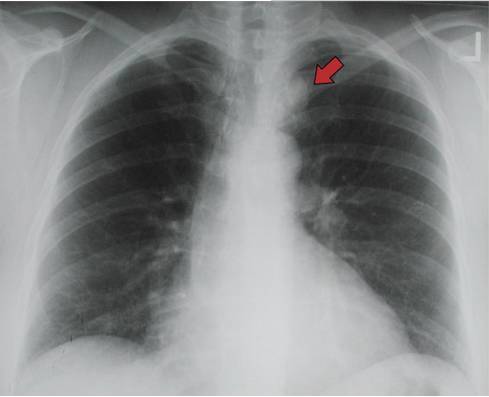

看胸片的16个关键点

28岁女 图一是胸片 图二是医生画的小圈那个地方是觉得有问题的地方

正常胸片和异常胸片

胸片怎么看